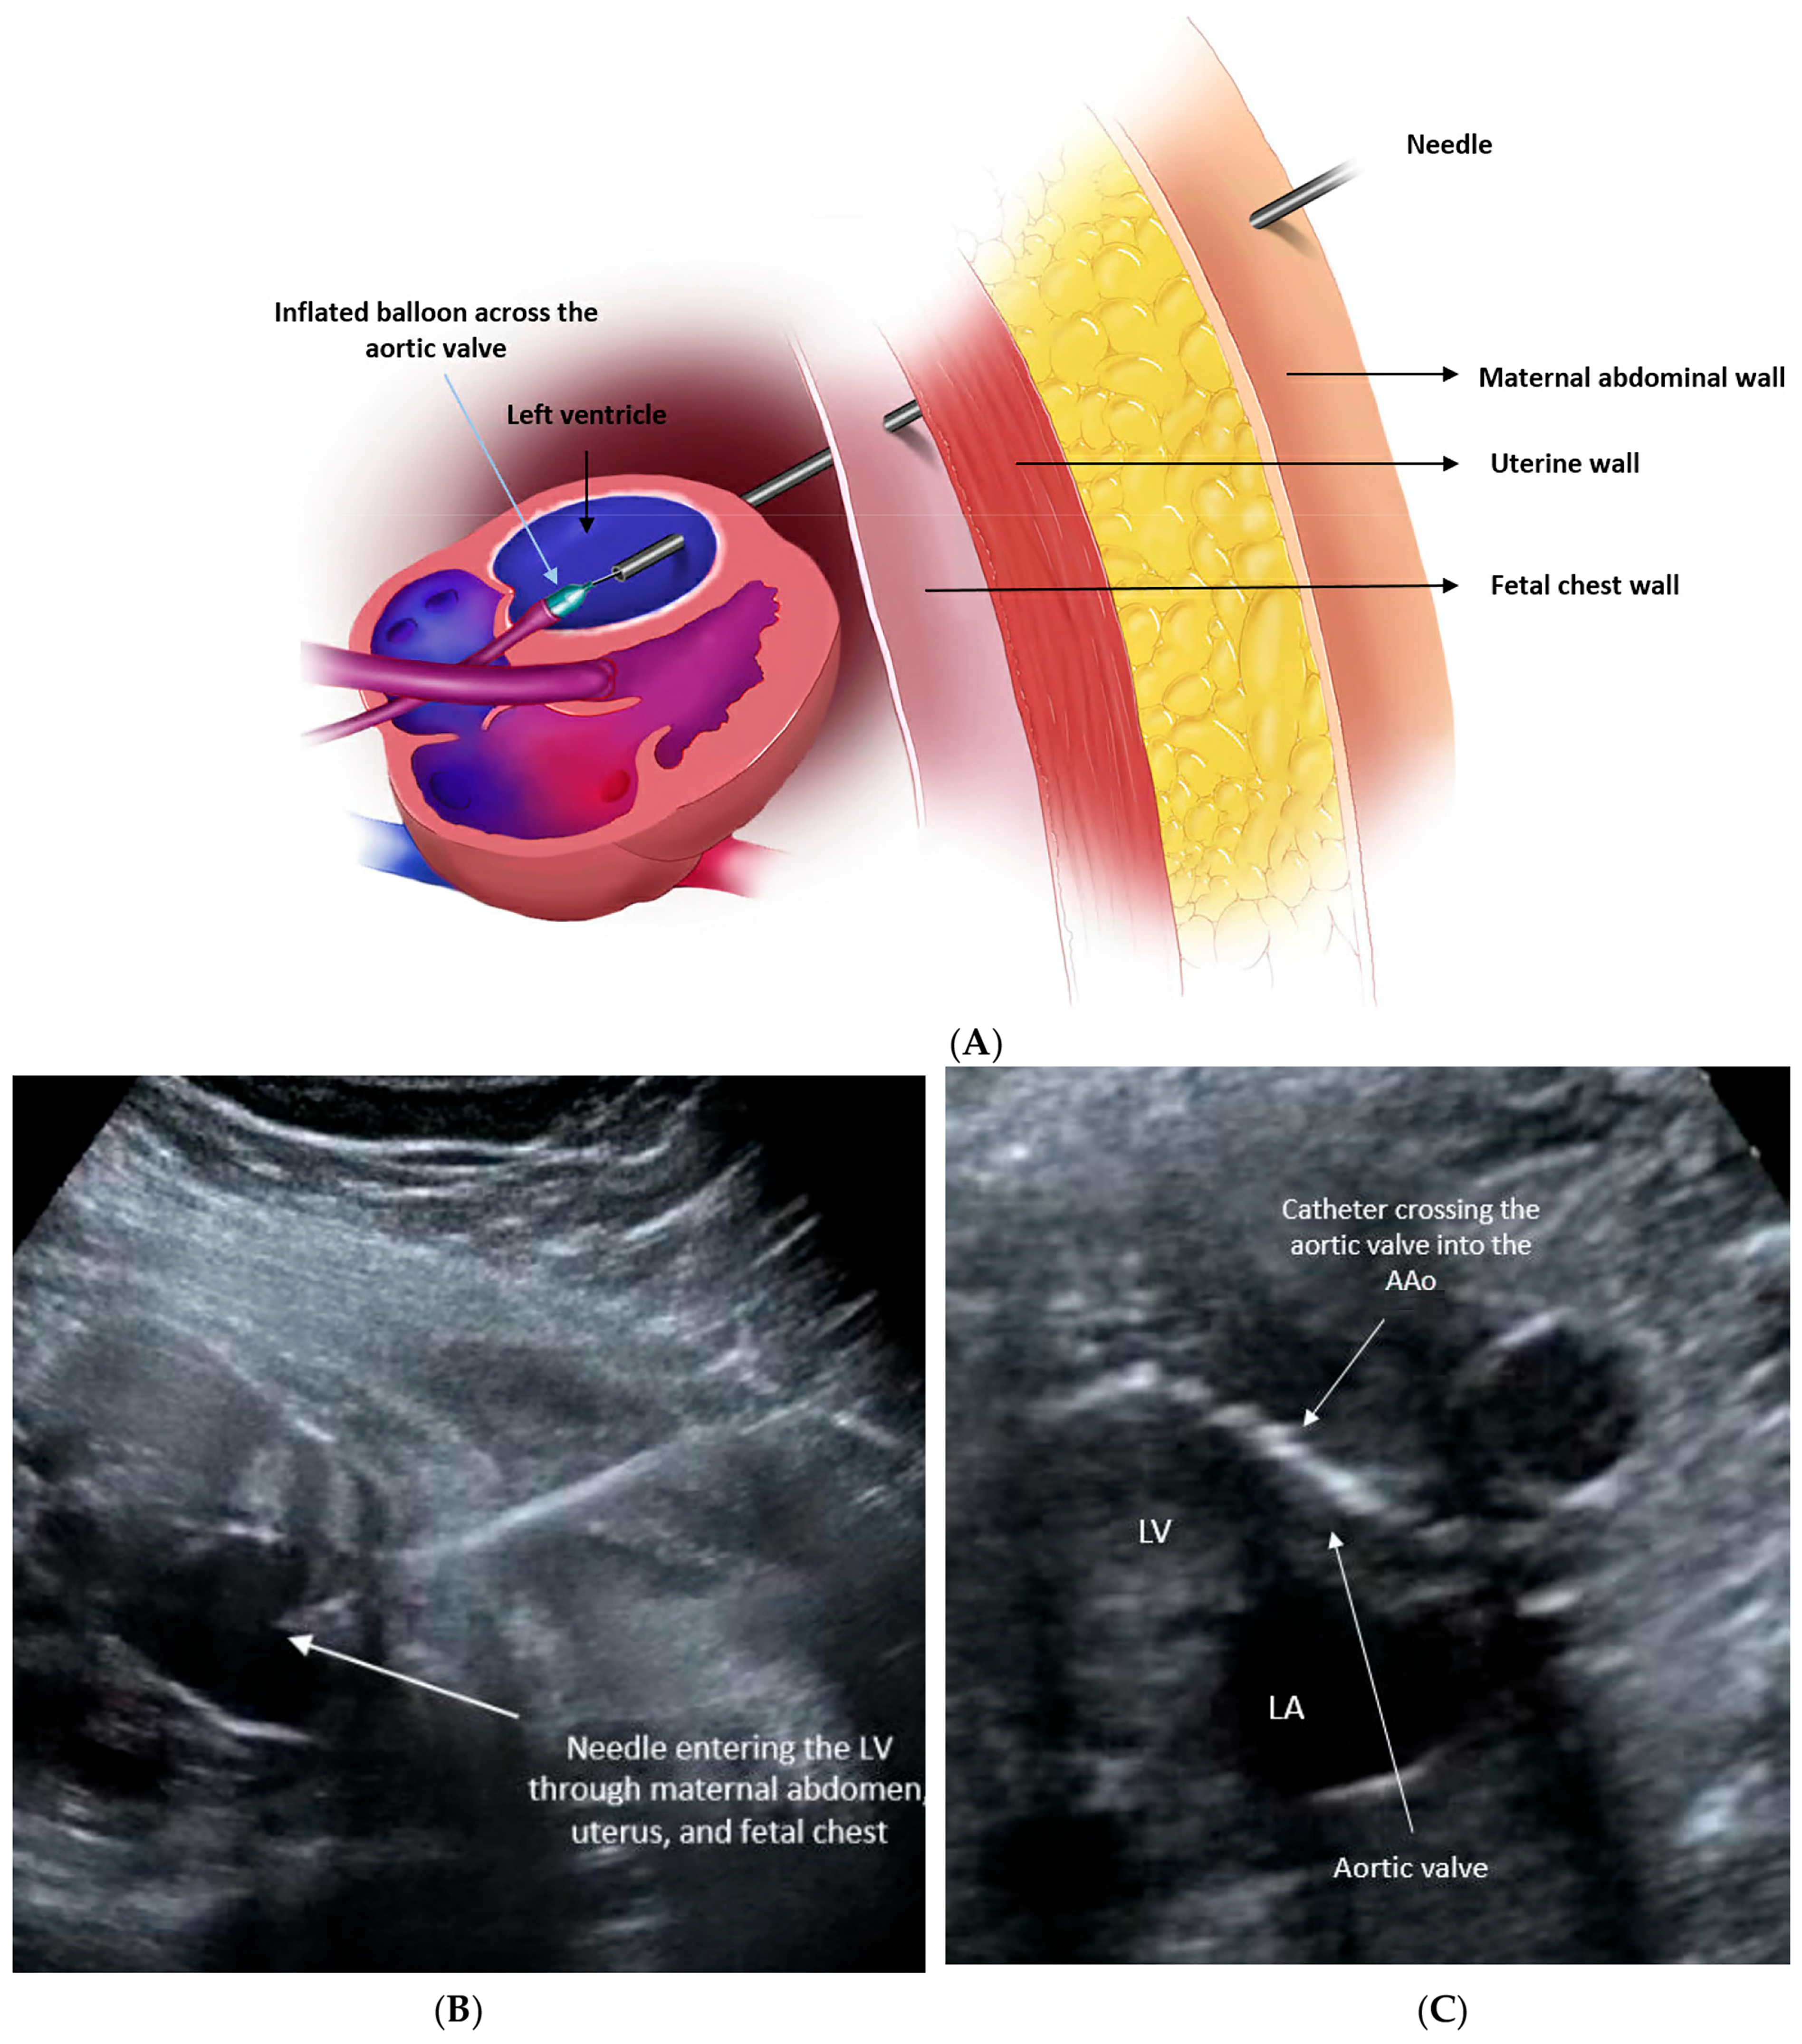

2.2. Procedural Technique